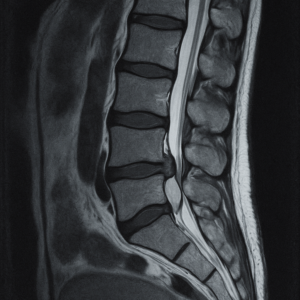

| 【得意なこと】 ・画像検査(レントゲン/MRI) ・診断名の確定 ・薬や注射による鎮痛 |

| 【こんな時におすすめ】 ・激痛で動けない ・足に力が入らない ・排尿障害がある |